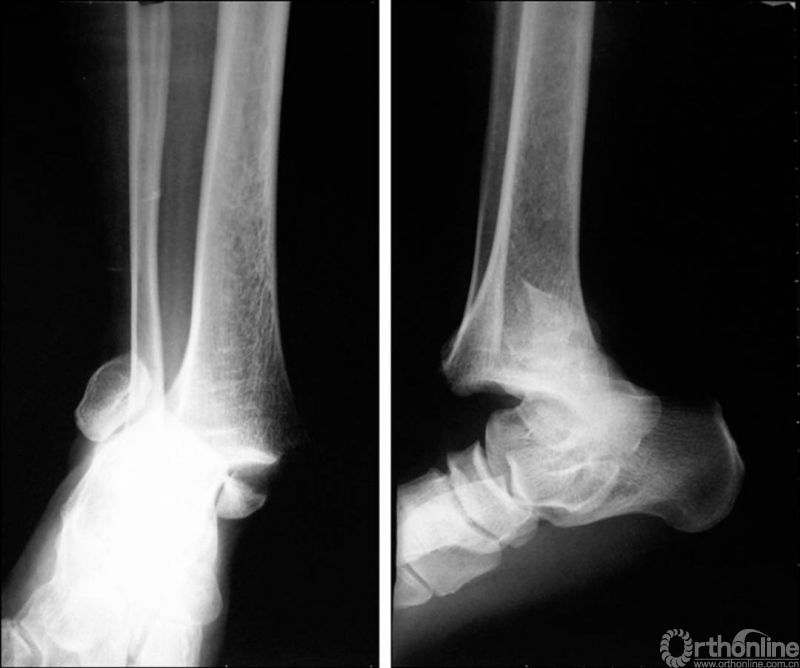

X线诊断:标准的踝关节影像学评估应包括3个位相:前后位(图5),踝穴位(内旋15°)(图6),侧位(图7)。

图5 前后位

图6 踝穴位(内旋15°)